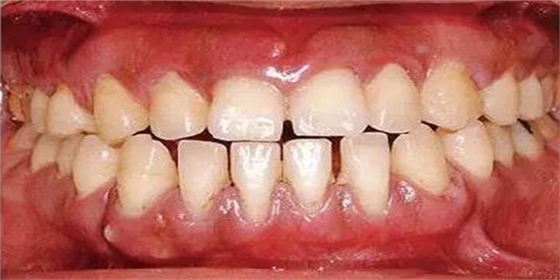

●33歲男性 侵襲性牙周炎廣泛型口腔內(nèi)照片

33歲男性,吸煙(1天10根,12年吸煙史)。菌斑控制狀況不好,牙周探診全頜牙周袋深5~10mm之外,全頜性牙周袋出血,部分牙周袋有排膿現(xiàn)象。X片可觀察到全頜性重度骨吸收。通過以上檢查可診斷出該患者為侵襲性牙周炎廣泛型。視診可知牙齦雖然有炎癥,但沒有出現(xiàn)嚴(yán)重浮腫,沒有大量牙結(jié)石沉積。